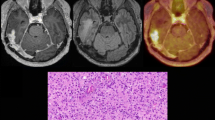

Serial MRI and FET PET scans of a 36-year-old woman after surgery for an anaplastic astrocytoma WHO III and following two RIT cycles (10/99 and 11/99 with 2,460 MBq 131I-TN-mAb). The patient was clinically tumour free at follow-up for up to 77 months after surgery. Slight linear contrast enhancement surrounding the small tumour cavity in the right central area is observed on MRI. On FET PET there is slightly increasing homogeneous FET uptake surrounding the cavity (which in this particular case mimics a more focal appearance owing to the small lesion size in combination with the limited resolution of the PET scanner), peaking 15 months after RIT (02/01) and decreasing during further follow-up. The respective TUmax/BG ratios are given below the PET images

Among the 17 of 24 patients who ultimately presented with tumour progression, ten experienced tumour recurrence and seven, regrowth of residual tumour. These diagnoses were histopathologically proven by stereotactic biopsy in five patients and by re-operation in three patients. In the remaining nine patients, suspected tumour regrowth or recurrence was assumed because of concordantly increasing contrast enhancement on MRI and clinical deterioration. Table 2 summarises the characteristics and results of patients with progressive disease. The ten patients without obvious tumour at baseline initially presented with normal ratios (TUmax/BG 1.64±0.26) but showed focally increasing FET uptake values, resulting in pathological ratios during follow-up (TUmax/BG 2.67±0.43). A representative example is shown in Fig. 2. In seven patients with known residual tumour on the baseline scan, further FET PET investigations demonstrated pathological ratios which were stable or increased over time (baseline TUmax/BG 2.49±0.42; last follow-up TUmax/BG 3.04±0.49). Six of these seven patients showed pathological contrast enhancement on baseline MRI as well. Most interestingly, in one of the seven patients (with anaplastic astrocytoma WHO grade III), MRI was rated as normal owing to the lack of contrast enhancement, whereas the concomitant PET scan showed pathological focal FET uptake ventral of the cavity, clearly indicating recurrence. This was proven by stereotactic biopsy. This patient underwent re-operation of this area, but unfortunately developed another tumour manifestation distant from the primary location that showed contrast enhancement on MRI as well (Fig. 3).

Serial MRI and FET PET scans of a 30-year-old man after surgery and radiation therapy of an anaplastic astrocytoma WHO III located in the right parietal lobe before and after 1 RIT cycle (07/02 with 1870 MBq 131I-TN-mAk). a At baseline and 3 months after therapy, slightly increased homogeneous FET uptake at the cavity borders with additional nodular FET uptake ventral of the cavity indicating recurrence. MRI shows no suspicious contrast enhancement. b After reoperation development of another tumour manifestation developed distant the primary location with focal FET uptake and contrast enhancement on MRI as well. The respective TUmax/BG ratios are given below the PET images